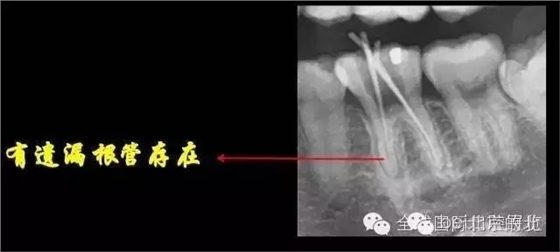

DB,DL.根管充填完成,樹脂封閉根管口,繼續(xù)探索未知的近中隱藏根管,所以決定拍1/4 CBCT確認(rèn)MB存在, 其實(shí)預(yù)備的是MM和ML,

證實(shí)確實(shí)是遺漏了MB,